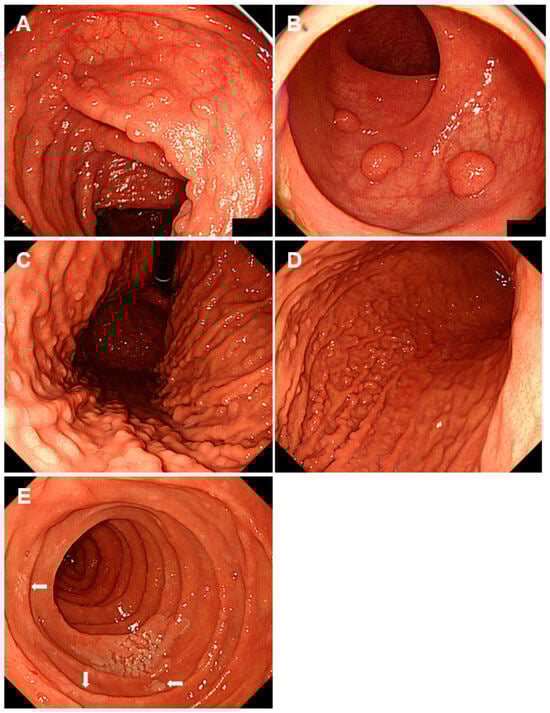

| Familial adenomatous polyposis | Mutations in the APC gene | Multiple fundic gland polyps are typical. Intestinal-type adenomas and early gastric cancers exhibit reddish depressed lesions, while gastric-type adenomas display whitish elevated lesions. |

| Peutz-Jeghers syndrome | Mutations in the STK11 gene | Solitary or sporadic polyps larger than 5 mm exhibiting a reddish color with a sessile or semi-pedunculated morphology (hyperplastic polyps and Peutz-Jeghers polyps), and multiple sessile polyps of 5 mm or smaller, mirroring the color of the peripheral mucosa (fundic gland polyps and hyperplastic polyps). |

| Cowden syndrome | Mutations in the PTEN gene | Polyps generally exhibit a color similar to the peripheral mucosa but may also be reddish (hyperplastic, hamartomatous, inflammatory, lipomatous, fibromatous, and adenomatous polyps). |

| GAPPS | Mutations in the APC exon 1B promotor region | Polyps localized in the gastric body and fornix, predominantly constituted by fundic gland polyps manifesting as regions of dysplasia and adenocarcinoma in some patients. |

| Neuroendocrine tumors in autoimmune gastritis | Autoimmune gastritis | Yellow or red tumors are identified in the gastric body with marked or prevailing atrophy localized within the gastric body while sparing the gastric antrum. |

| Proton pump inhibitor-related gastric mucosal changes | Prolonged intake of proton pump inhibitors | Multiple white and flat elevated lesions, cobblestone-like mucosa, the emergence and enlargement of the fundic gland, and hyperplastic polyps. |

| Multiple submucosal heterotopic glands | Chronic inflammation, such as infection of Helicobacter pylori | Polypoid lesions with cystic areas beneath the gastric mucosa visualized during an endoscopic ultrasound examination. |